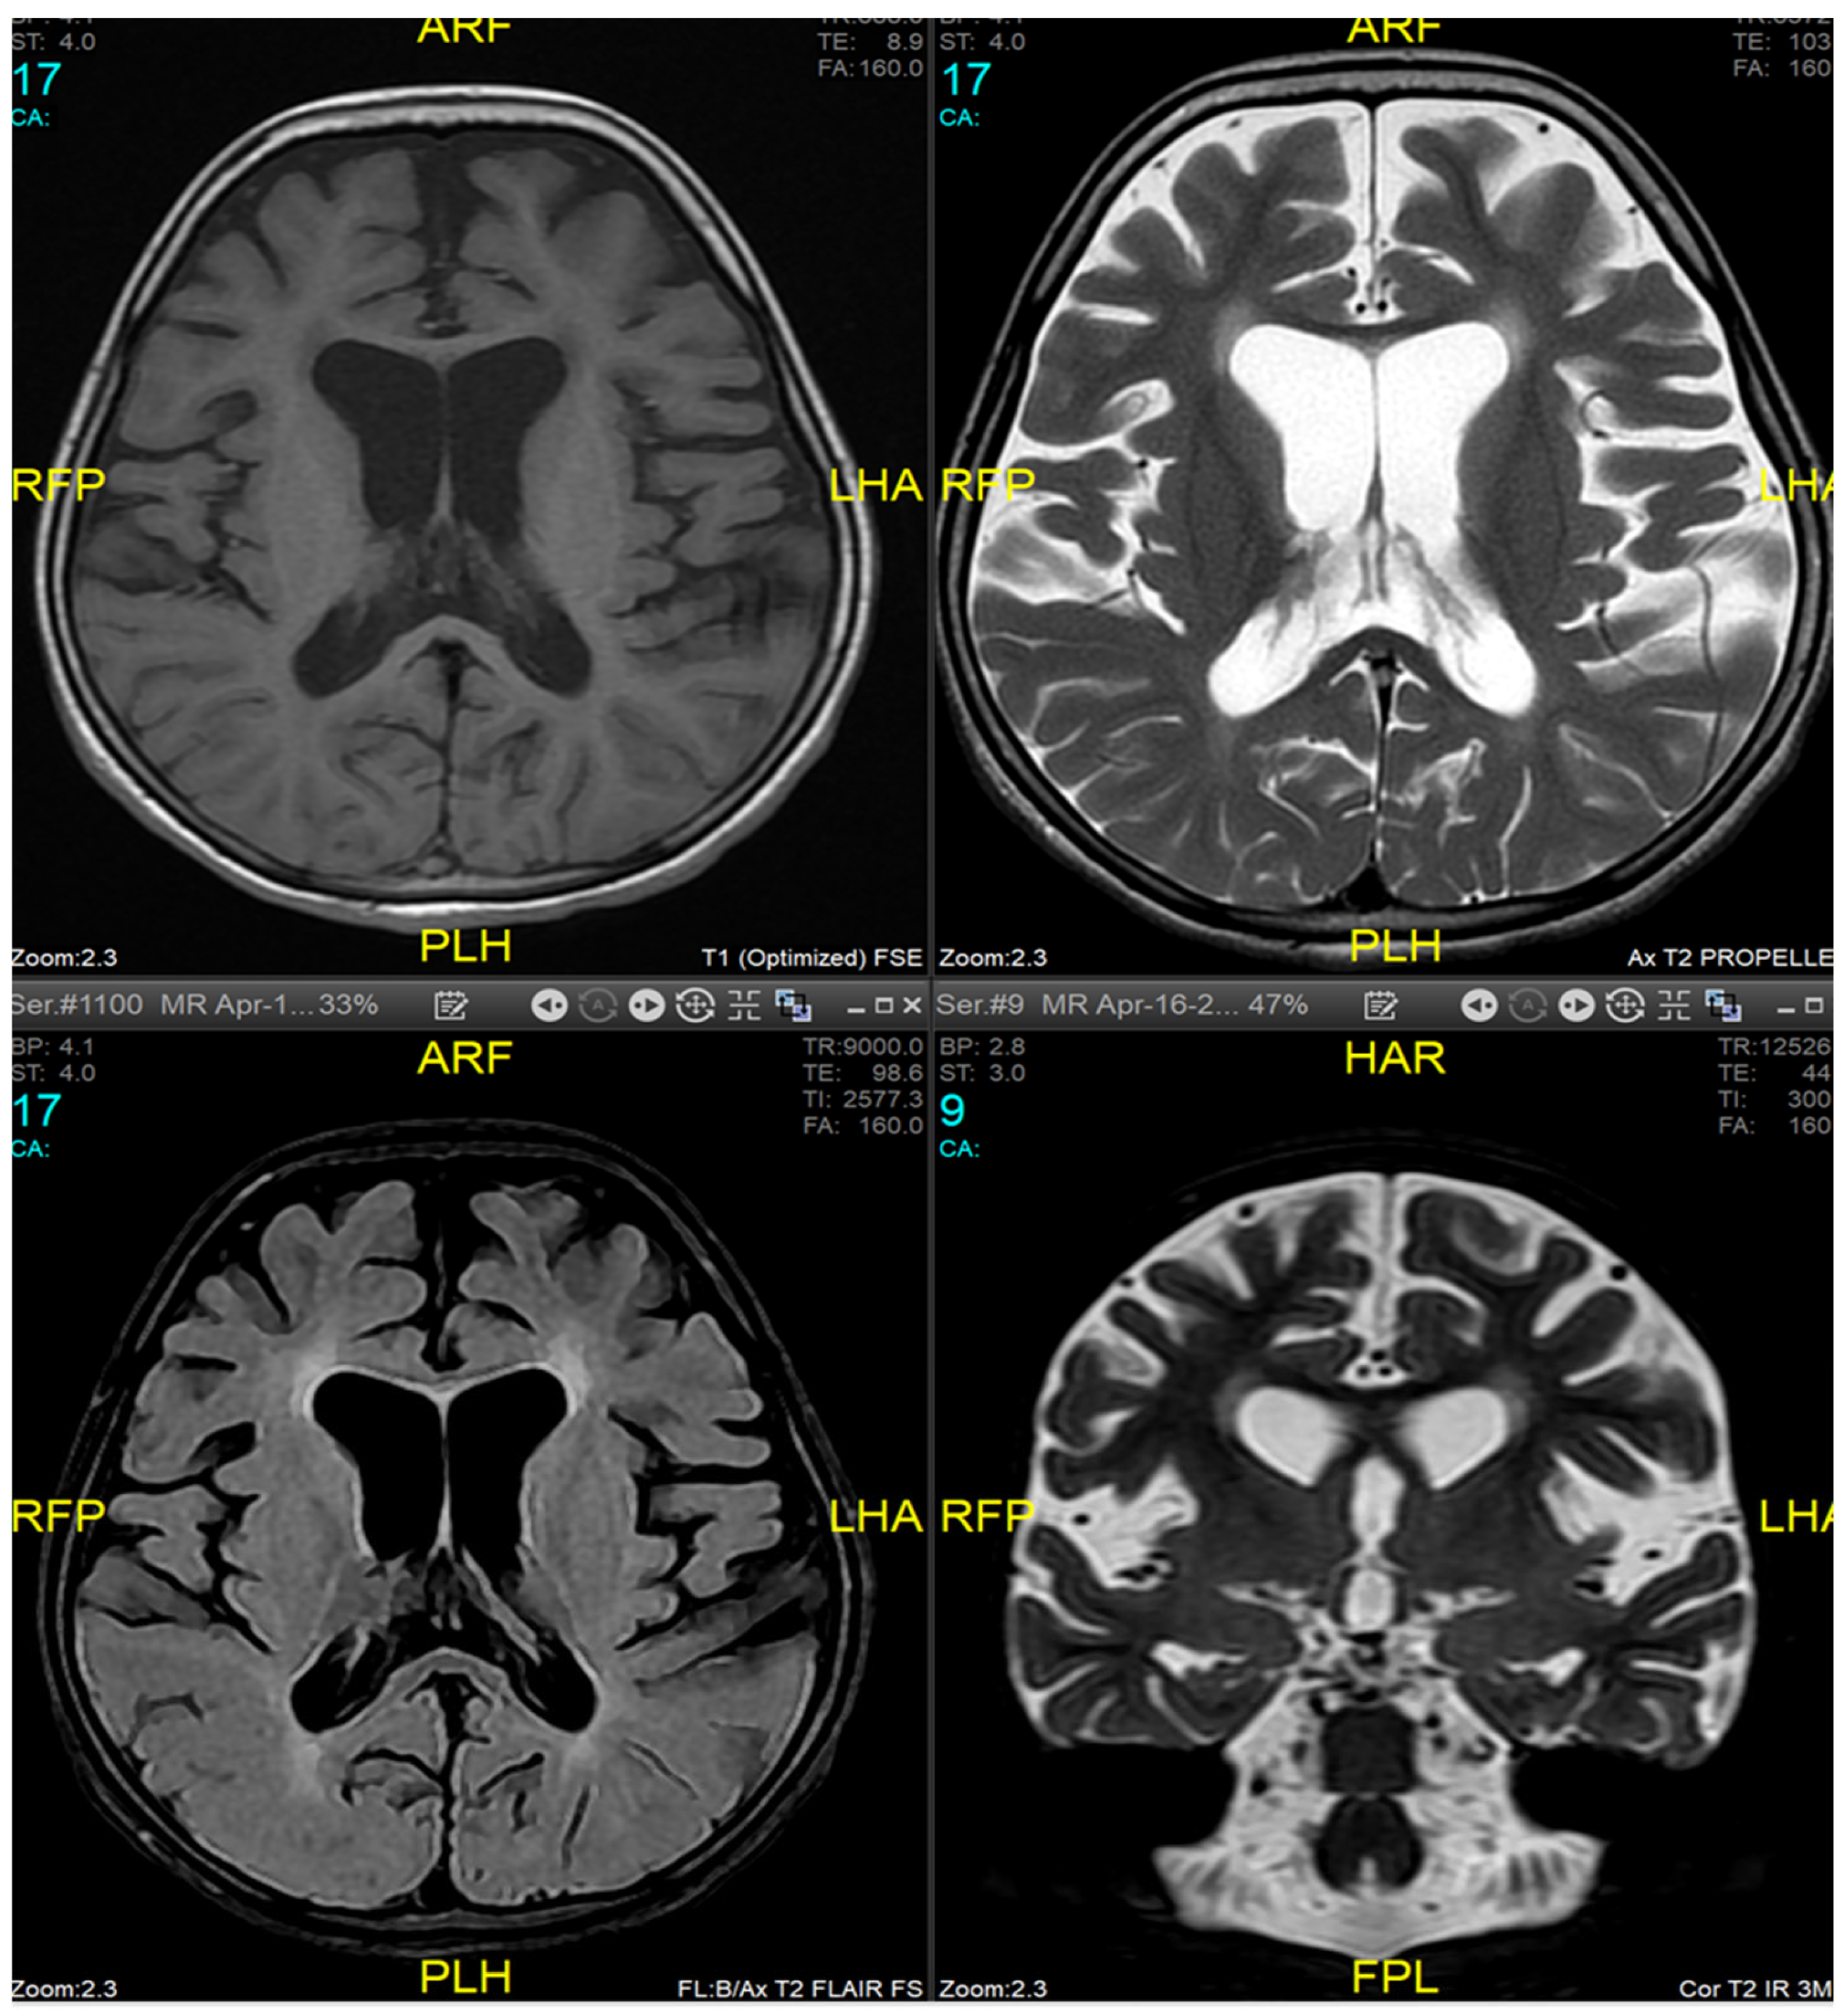

Magnetic resonance imaging (MRI) of the brain and genetic analysis were done to support the diagnosis. Her MRI now showed newly developed generalized atrophic changes of the brain, characterized by supra and infratentorial ventricular dilatation, prominent cortical sulci, and extra-axial CSF spaces such as Sylvian fissures and basal cistern. The diffuse deep periventricular white matter showed high signal intensities on T2/FLAIR (Fluid Attenuated Inversion Recovery) sequences. Additionally, there was global thinning out of the corpus callosum [Figure 1]. This was in contrast to her prior brain MRI at the age of 2.5 years which showed no evidence of atrophic brain changes or iron deposition [Figure 2].

MRI findings are variable depending on the disease stage at which imaging was performed [1,3,9,11]. Imaging may be completely normal in some patients, as was the case in our patient during the first presentation, making it insufficient to rule out INAD based on radiological findings only and necessitating follow up imaging later. Typical findings described include cerebral atrophy, white matter changes, and iron deposits in the globus pallidus, substantia nigra, and dentate nucleus [18,19]. Due to the presence of iron deposits, INAD can be classified as a subtype of neurodegeneration with brain iron accumulation diseases (NBIA). However, iron deposits are not specific to INAD [20]. Our patient exhibited typical MRI features, on a follow-up study, but did not have any evidence of iron accumulation in the brain.

Figure 1. Brain MRI at 9 years age (16 April, 2024) - Generalized atrophic changes of the brain, characterized by supra and infratentorial ventricular dilatation, prominent cortical sulci, and extra-axial CSF spaces such as Sylvian fissures and basal cistern. The diffuse deep periventricular white matter showed high signal intensities on T2/FLAIR (Fluid At-tenuated Inversion Recovery) sequences. There was global thinning out of the corpus callosum.